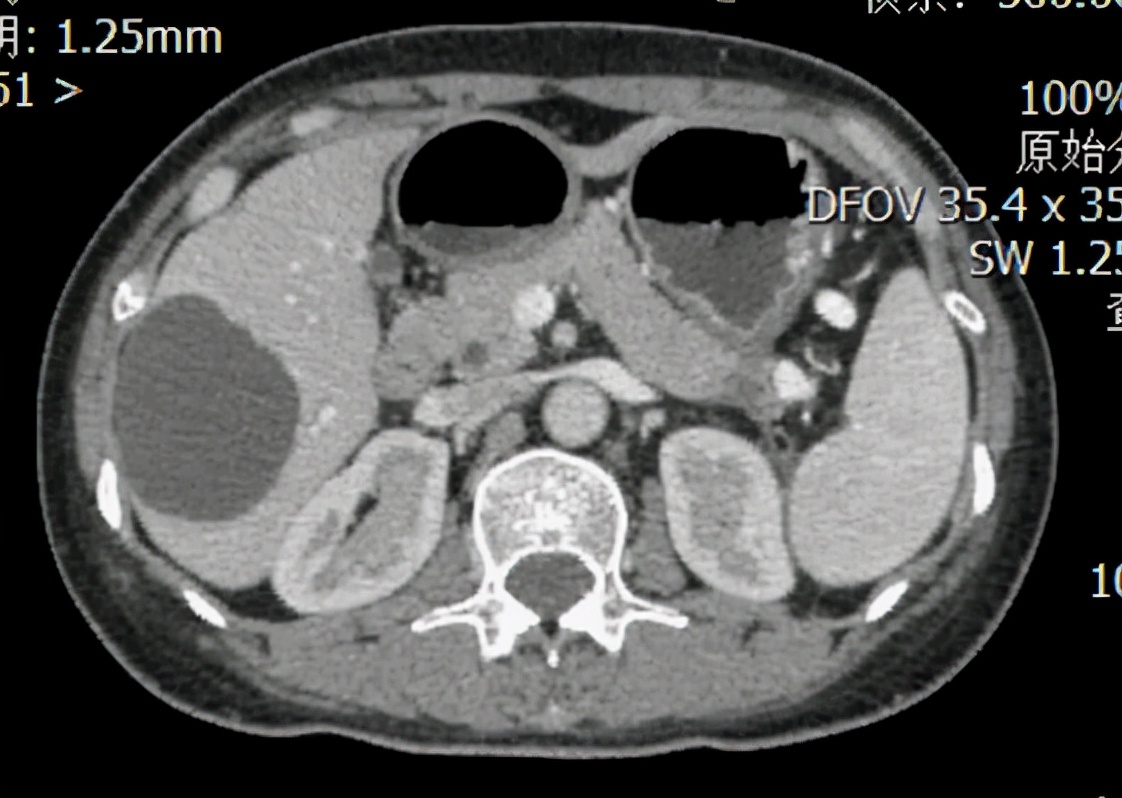

图1:患者2018年6月的CT图,红框为胰腺尾部原发灶,大小约6×7cm。

图2:患者化疗9周期后的CT图,红框为胰腺尾部原发灶,直径约1cm。